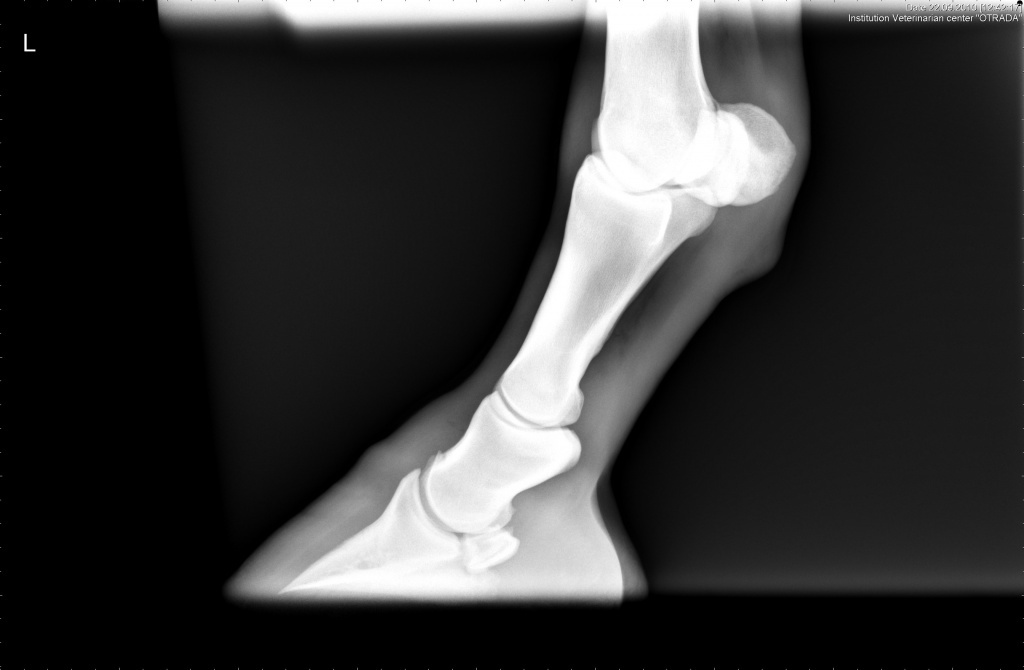

для сравнения снимок без перелома